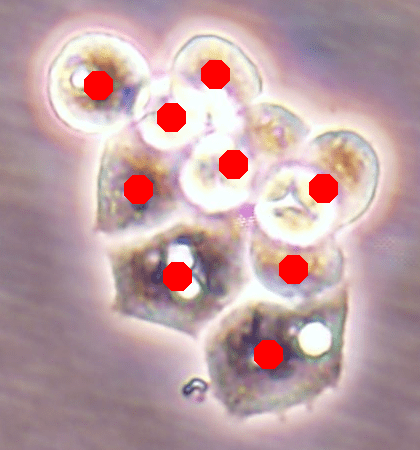

Before the advances in deep learning, the traditional approach for cell detection/segmentation is to employ low-level handcrafted features, reflecting color, edge, and shape characteristics of cells. This approach has given promising results when the features are defined properly, as a good representation of the visual cell characteristics. On the other hand, these characteristics may change from one cell type to another (see Fig. 1) and new features need to be defined to meet the cell characteristics of a new type. Additionally, when there exists heterogeneity in the visual characteristics of the same cell type, using a single model may not be sufficient to detect all cells of this type, particularly for cancer cells which are exploited more in high throughput screening.

![]() |

| (a) | (b) | (c) |

We test our DeepDistance model on three datasets, each of which consists of live cell images of a different cell line. They are the CAMA-1, MDA-MB-453, and MDA-MB-468 human breast cancer cell lines. The images in all datasets were acquired at magnification and pixel resolution. An example image from each dataset is shown in Fig. 1. As seen in this figure, cells might be visually different within and across different cell lines.